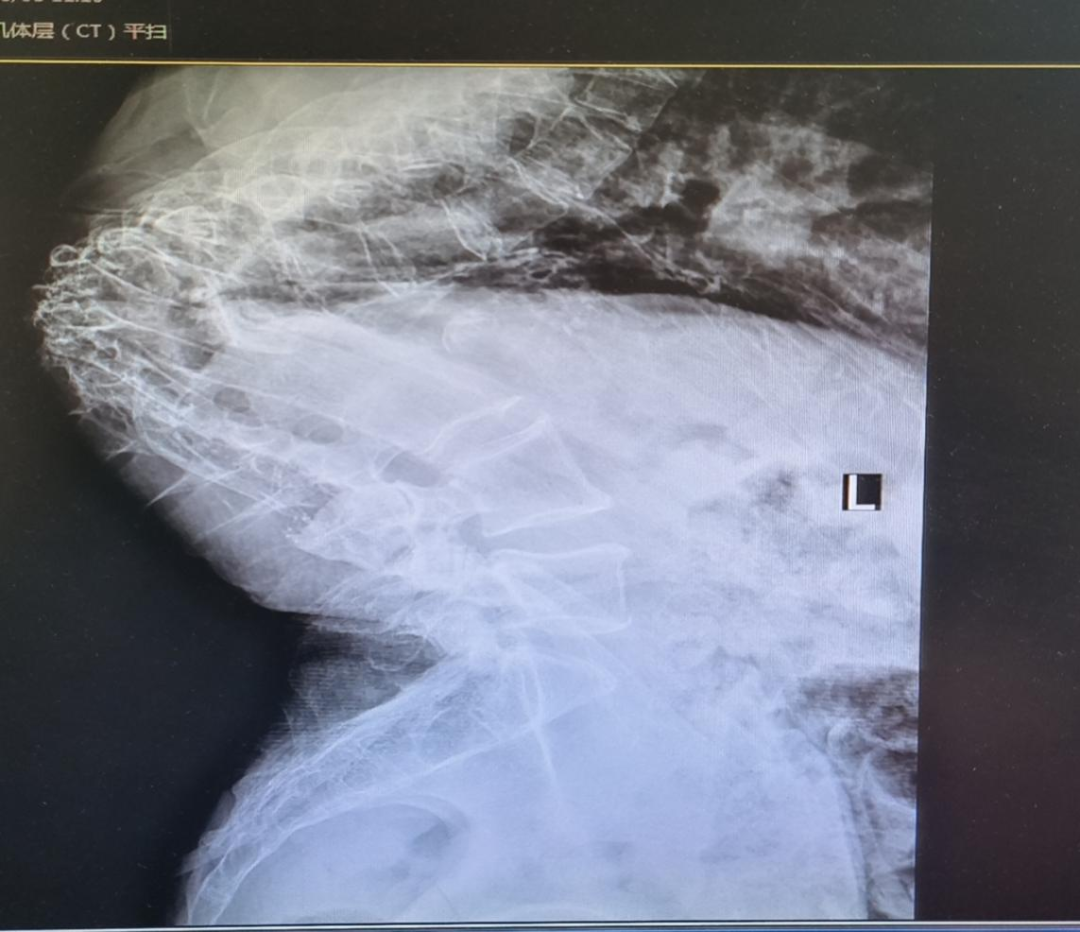

针对患者的特殊情况,主管医生张丰立即申请麻醉手术科进行MDT会诊。术前访视:患者严重驼背状态,桶状胸,不能久躺,查看相关化验室检查,胸部CT,脊柱正侧位DR,颈椎活动度、张口度,发现马氏分级Ⅲ~Ⅳ级,存在困难气道。为保证手术的顺利进行,麻醉手术科利用晨会对该患者进行了讨论,当前面临的首要困难是能否为患者顺利建立人工气道?由于没有纤支镜,对实施气管插管是一个挑战,最终团队决定,患者入室后先将患者摆成V型体位,评估患者是否正常面罩通气,若能正常通气,可快速诱导插管;若面罩不能正常通气,则保留自主呼吸。在充分表麻及镇静下可视喉镜下插管,术前准备好各种抢救药品及设备,最终患者在快速诱导可视喉镜下顺利建立人工气道,在麻醉医生、护士、手术医生默契配合下,手术历时1.5小时,顺利完成。